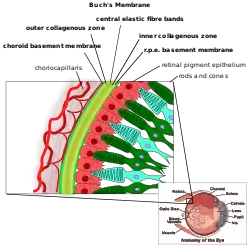

Detailed illustration showing the bruch's membrane and its layers. | |

Bruch's membrane consists of five layers (from inside to outside):[2][3]

- the basement membrane of the retinal pigment epithelium

- the inner collagenous zone

- a central band of elastic fibers

- the outer collagenous zone

- the basement membrane of the choriocapillaris